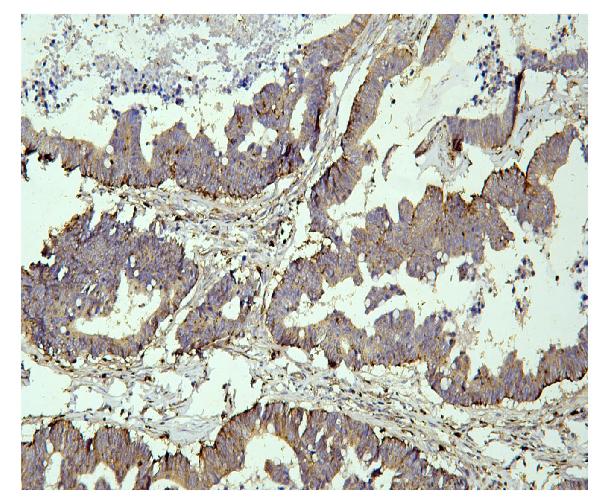

IHC analysis of PPT1 using anti-PPT1 antibody (M02690).

PPT1 was detected in a paraffin-embedded section of human intestinal cancer tissue. Biotinylated goat anti-mouse IgG was used as secondary antibody. The tissue section was incubated with mouse anti-PPT1 Antibody (M02690) at a dilution of 1:200 and developed using Strepavidin-Biotin-Complex (SABC) (Catalog # SA1021) with DAB (Catalog # AR1027) as the chromogen.